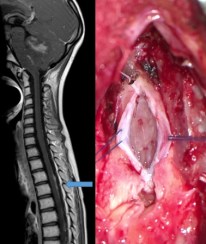

on recherche systématiquement des métastase par l‘IRM cranio-spinale.

la chirurgie a pour but premier le diagnostic histopathologique, qui peut être obtenu par abord direct de la tumeur, ou par abord d’une métastase, si la lésion à biopsier est de volume suffisant pour obtenir le diagnostic histopathologique et le grading de biologie moléculaire.

lorsque la masse tumorale métastatique est volumineuse, une chirurgie de debulking peut être nécessaire afin de préparer le patient pour la radio-chimiothérapie.